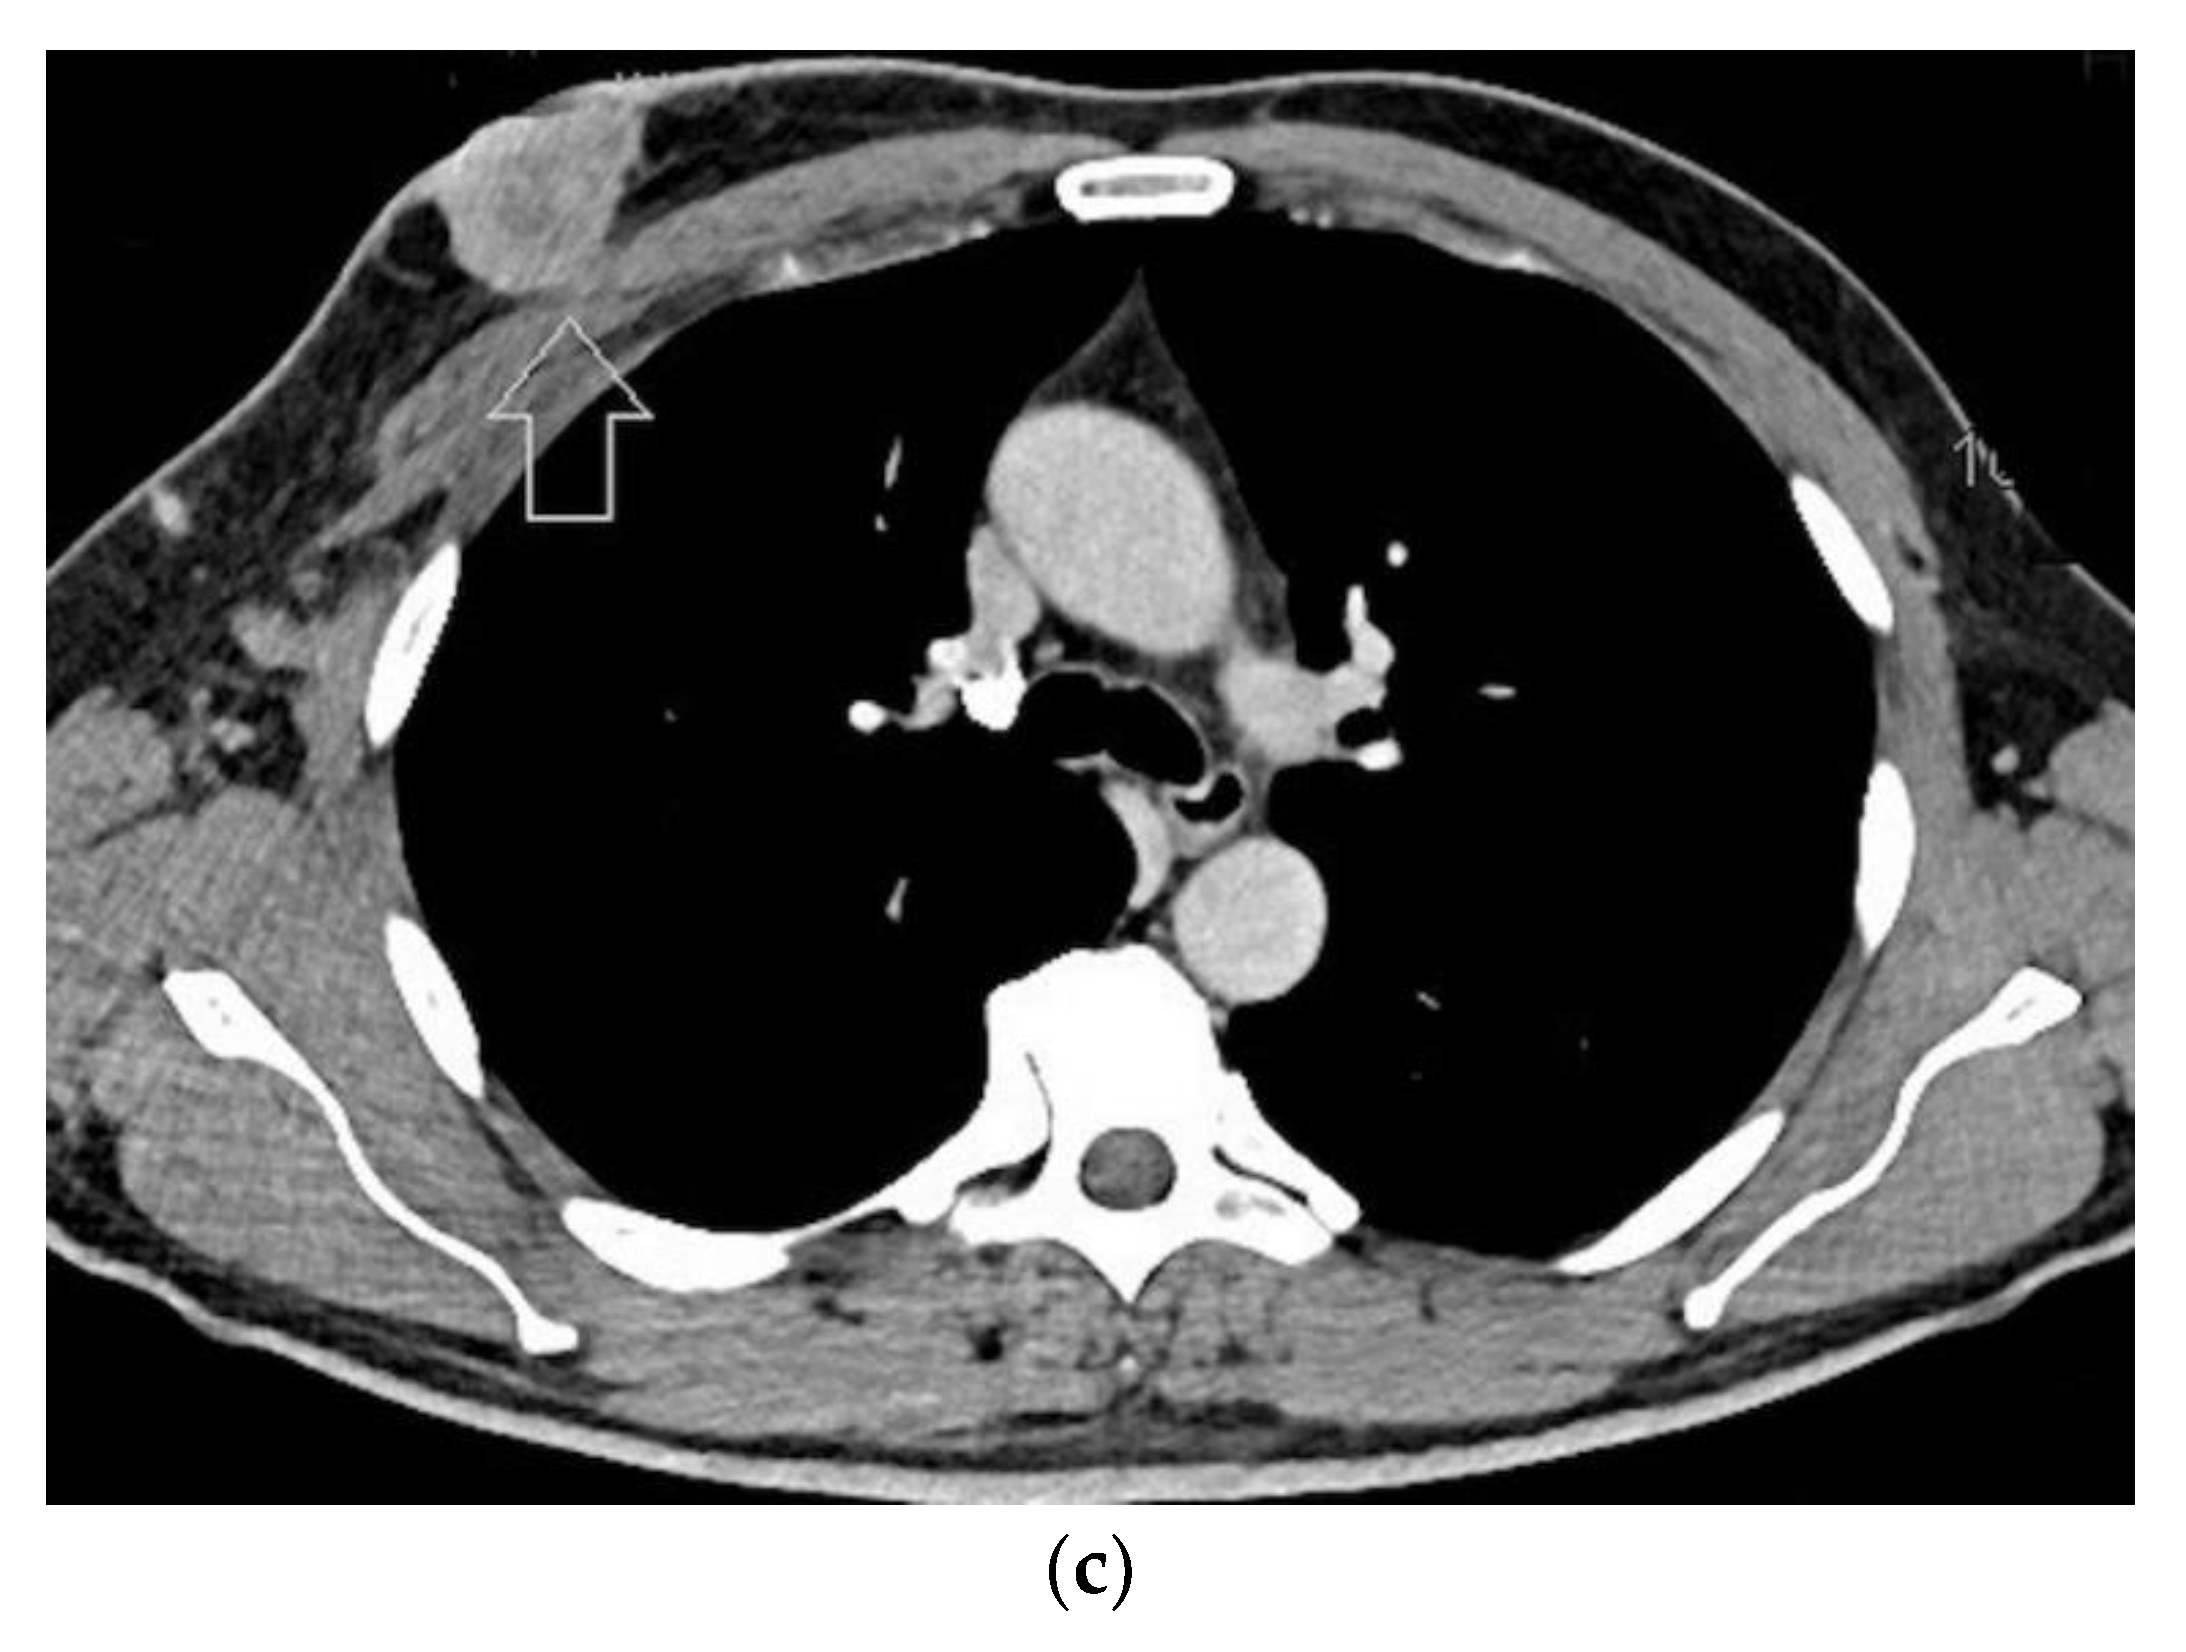

Finally, the male breast is also thin, except in the case of marked lipomastia or gynecomastia. Male breast abnormalities are usually located in the retroareolar region, but they can develop in any area. In clinical practice, the main need is to differentiate unilateral, or apparently unilateral, gynecomastia from breast carcinoma. Other uncommon abnormalities of the male breast include abscess, hematoma, diabetic mastopathy, foreign bodies, and benign tumors. All these changes are optimally depicted using high-frequency probes (Figure 12) [4].

Figure 12. Locally advanced male breast cancer. Clinical picture (a), high-resolution sonography scan (b), and computed tomography scan in the portal phase of the breast lesion (c). The use of the high-frequency transducer allows the depiction of the tumor tissue infiltrating the nipple–areolar complex.